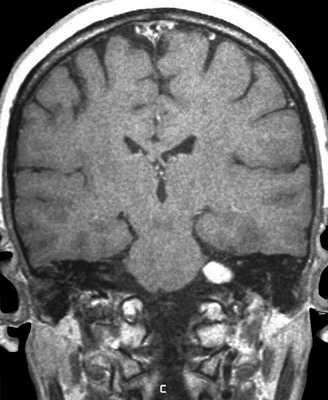

Классификация по Koos: I стадия: опухоль находится в пределах внутреннего слухового прохода, диаметр внутриканальной части составляет 1—10 мм; II стадия: опухоль вызывает расширение канала внутреннего слухового прохода и выходит в ММУ, ее диаметр составляет 11—20 мм; III стадия: опухоль распространяется до ствола головного мозга без его компрессии, диаметр составляет 21—30 мм; IV стадия: опухоль вызывает компрессию ствола головного мозга, ее диаметр более 30 мм. Ганноверская классификация по M. Samii: Т1 — интрамеатальная опухоль; Т2 — интра-экстрамеатальная опухоль; Т3а — опухоль заполняет мостомозжечковую цистерну; Т3b — опухоль распространяется до ствола головного мозга; Т4а — опухоль вызывает компрессию ствола; Т4b — опухоль грубо деформирует ствол мозга и IV желудочек (рис. 1) Рис. 1. МРТ головного мозга с контрастом. Примеры градации ВШ по Ганноверской классификации. a — Т1, интрамеатальная опухоль; б — Т2, интраэкстрамеатальная опухоль; в — Т3а, опухоль заполняет мостомозжечковую цистерну; г — Т3b, опухоль распространяется до ствола головного мозга; д — Т4а, опухоль вызывает компрессию ствола; е — Т4b, опухоль грубо деформирует ствол и IV желудочек. [7, 8].

МРТ головного мозга. Т2-взвешенная корональная МРТ. Невринома слухового нерва, цветовая обработка изображения.

На Т2-взвешенных МРТ головного мозга невриномы имеют округлую или овальную форму, изоинтенсивны или слегка гиперинтенсивнее белого вещества, хорошо видны на фоне яркого ликвора цистерны. Крупные опухоли могут подвергаться кистозной дегенерации и включать сосуды. Мелкие невриномы имеют компонент во внутреннем слуховом проходе и как бы “утолщают“ нерв на МРТ изображениях. Как показывает опыт МРТ СПб полностью внутриканальцевые невриномы встречаются редко. МРТ в СПб при шванномах мы проводим обычно с контрастированием. Контрастирование неврином при МРТ с контрастированием хорошее, обычно однородное. Нельзя забывать, что во внутреннем слуховом проходе также может быть воспалительный процесс (неврит), приводящий к сходной клинической симптоматике. При МРТ неврит виден как отёк нерва, имеется контрастное усиление на МР томограммах.

МРТ головного мозга. Невринома слухового нерва слева с внутриканальцевым компонентом. Аксиальные Т1-зависимая МРТ, Т1-зависимая МРТ с контрастированием, и корональная Т1-зависимая МРТ с контрастированием.